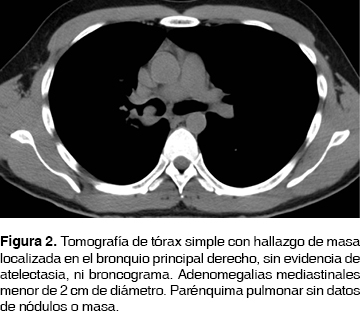

Paciente masculino de 37 años, con antecedentes de asma durante la infancia; presentó un neumotórax derecho espontáneo primario hace 15 años, tratado con colocación de sonda pleural por cuatro días, secundario a bulas congénitas. Hace cinco años funduplicatura de Nissen (360o) sin complicaciones. Previo a su ingreso al hospital presentó disnea de grandes a medianos esfuerzos, sibilancias audibles a distancia, motivo por el que se le realiza radiografía de tórax en proyección posteroanterior (figura 1), siendo reportada como normal; se inicia tratamiento con bromuro de ipatropio/salbutamol y ceftriaxona, con mejoría parcial del cuadro. A los tres días de haber iniciado el tratamiento presenta tos con escasos hemoptoicos intermitentes, situación por la que asiste a urgencias en donde se le realiza tomografía simple de tórax (figura 2) con presencia de una masa a nivel del bronquio principal derecho, así como presencia de adenomegalias mediastinales.

Por los hallazgos mencionados y como parte del protocolo se le realizó PET-CT (figura 3) encontrando una masa en bronquio principal derecho con actividad metabólica de 12 SUV. Se realizó una broncoscopia con los siguientes hallazgos: en la emergencia del bronquio principal derecho a 1.5 cm de la carina principal, había una lesión (figura 4) que abarcaba más del 90% de la luz del bronquio principal derecho. La lesión contaba con bordes bien definidos, despulidos, blanquecinos y fácilmente sangrantes (figura 5). Se tomaron biopsias por pinza, cepillado y lavado bronquial. La citología de lavado y cepillado bronquial fue positiva para células neoplásicas malignas que favorecen a linfoma (figura 6), las biopsias bronquiales reportaron infiltración por linfoma anaplásico de células grandes, ALK-1 positivo (CD45RO+/EMA+/CD30+) (figura 7), la biopsia de médula ósea negativa a infiltración, serología para VIH negativa. Se estableció un esquema de quimioterapia a base de ciclofosfamida, hidroxidoxorrubicina, vincristina y prednisona. La consulta de control a los tres meses del diagnóstico con resultado de PET-CT de control reportó masa en bronquio derecho con actividad metabólica de 3 SUV, no evidenció otras lesiones con actividad metabólica. Se continuó seguimiento por consulta externa.

Bazot et al.5 en su serie establecieron que los hallazgos radiológicos habituales en el linfoma primario pulmonar se aprecian como una ocupación alveolar en el 50-90% de los casos, con un diámetro menor de 5 cm y con un borde bien delimitado; la serie reporta hasta un 50% de los casos con presencia de broncograma aéreo. La tomografía computada, estudio que cuenta con mayor sensibilidad, ha demostrado que las lesiones son bilaterales (60-70%) y múltiples (70-77%). Menos del 10% de los pacientes tienen opacidades reticulonodulares difusas bilaterales, atelectasias o derrame pleural. En nuestro estudio, en la tomografía de tórax y como complemento del PET-CT, sólo se definió la presencia única de una masa en bronquio principal derecho.